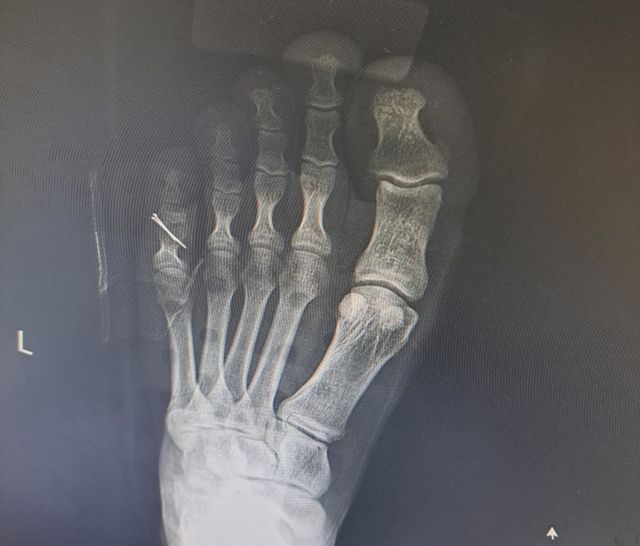

철심을 박은 A 병장 발 엑스선 촬영 사진. / 연합뉴스

A 병장은 전치 6주를 진단받고 다음 날 바로 수술에 들어갔다. 인대와 뼈를 고정하기 위해 철심을 박는 수술이었다. 수술비를 포함해 300만원가량 치료비가 나왔다.